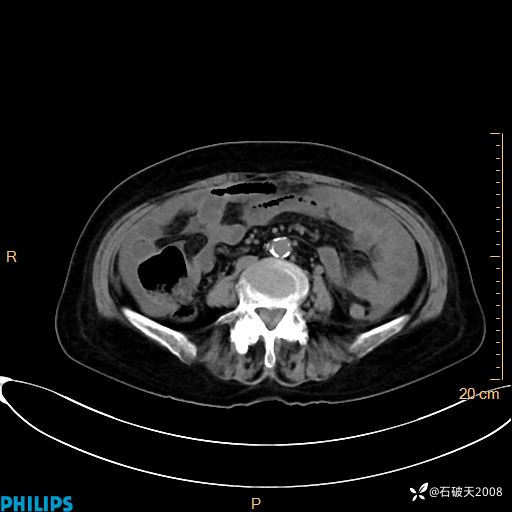

MIP